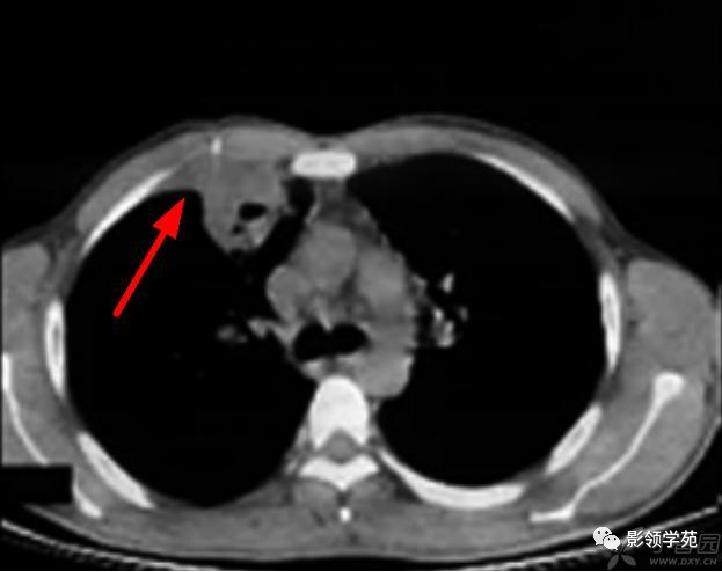

肺实变多由于肺泡出血所致,毛玻璃样密度影代表肺实变的早期阶段。楔形病灶是另一类较常见肺部CT 表现,肺梗死的病理基础是坏死性血管炎累及小动脉及小静脉引起的出血性肺梗死,CT表现为肺内楔形病灶,边缘清楚或不清楚,尖端指向肺门,宽基底位于胸膜面,可以看到血管进入征象及胸膜的增厚。

病例5:左下叶肺梗死,左肺下叶楔形病灶,边缘清楚,宽基底位于胸膜面,尖端指向肺门。